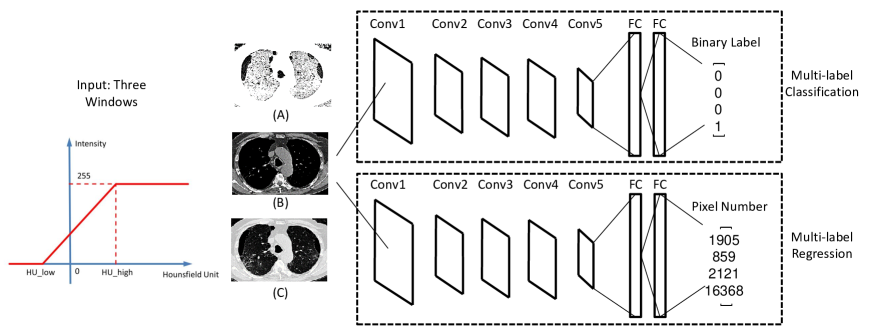

There are several mainstream CNN architectures, such as AlexNet [10], VGGNet [40], GoogLeNet [41], and deep residual networks [42]. Each network has its own advantages and is suitable for specific applications. Here we employ a variation of AlexNet, called CNN-F [43], for its good trade-off between efficiency and performance. Fully-annotated medical imaging datasets are usually of limited availability and can be much smaller than the popular computer vision ImageNet database [44]. The classical CNN-F contains five convolutional layers, followed by two fully-connected (FC) layers, and a last softmax layer for classification. We modify it to accommodate our application of detecting multiple ILD patterns in CT images, as shown in Fig. 2. Based on our empirical test using a much deeper CNN model of VGG-19, deeper models do not provide significantly noticeable quantitative performance boosts in ILD classification accuracy while at the same time they consume much more training and testing time.

To better capture the abnormal ILD patterns in CT images, we select three CT attenuation ranges or windows and rescale them to for CNN input. This is inspired by the fact that radiologists adjust the CT contrast window to optimize the visualization effects for certain tissues or pathologies on CT scans. For example, “Lung” window visualizes details in lung tissue that are not apparent on the “Bone” window, whereas much of the information in bone and soft tissue will be lost on the “Lung” window. In this work, we use three CT attenuation scales to highlight different lung disease patterns. As demonstrated in Fig. 2(A), this process is designated to preserve the attenuation values between HU_low and HU_high via a linear transformation. The intensity values outside the specific attenuation window are set as 0 or 255. In details, the low attenuation range (Fig. 2(B)) is used to capture ILD patterns with lower intensities, such as emphysema; the normal range (Fig. 2(C)) to represent normal appearance of lung regions; and high attenuation range for highlighting patterns with higher intensities, for example, consolidation and nodules. In our experiments, the low attenuation window is set as HU_low and HU_high; for normal range, HU_low and HU_high; for high attenuation scale, HU_low and HU_high.